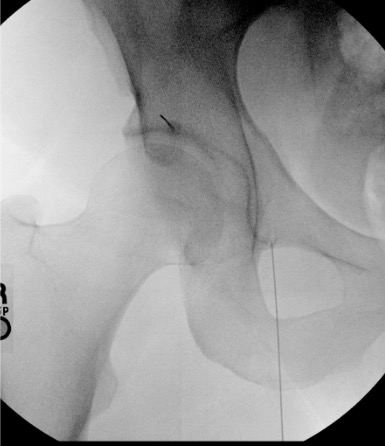

- Target: CT-guided; obturator foramen or medial to femoral vessels

- Approach: CT supine; coronal plane most useful; 22G needle

Steps

CT planning

Position + skin prep

Advance 22G needle to target

Contrast injection

Inject medication

CT confirm and withdraw